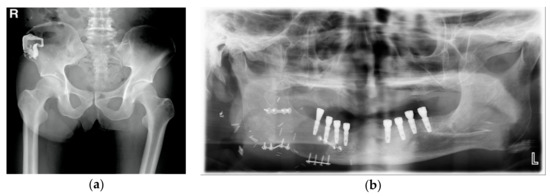

2.2. Surgical Technique